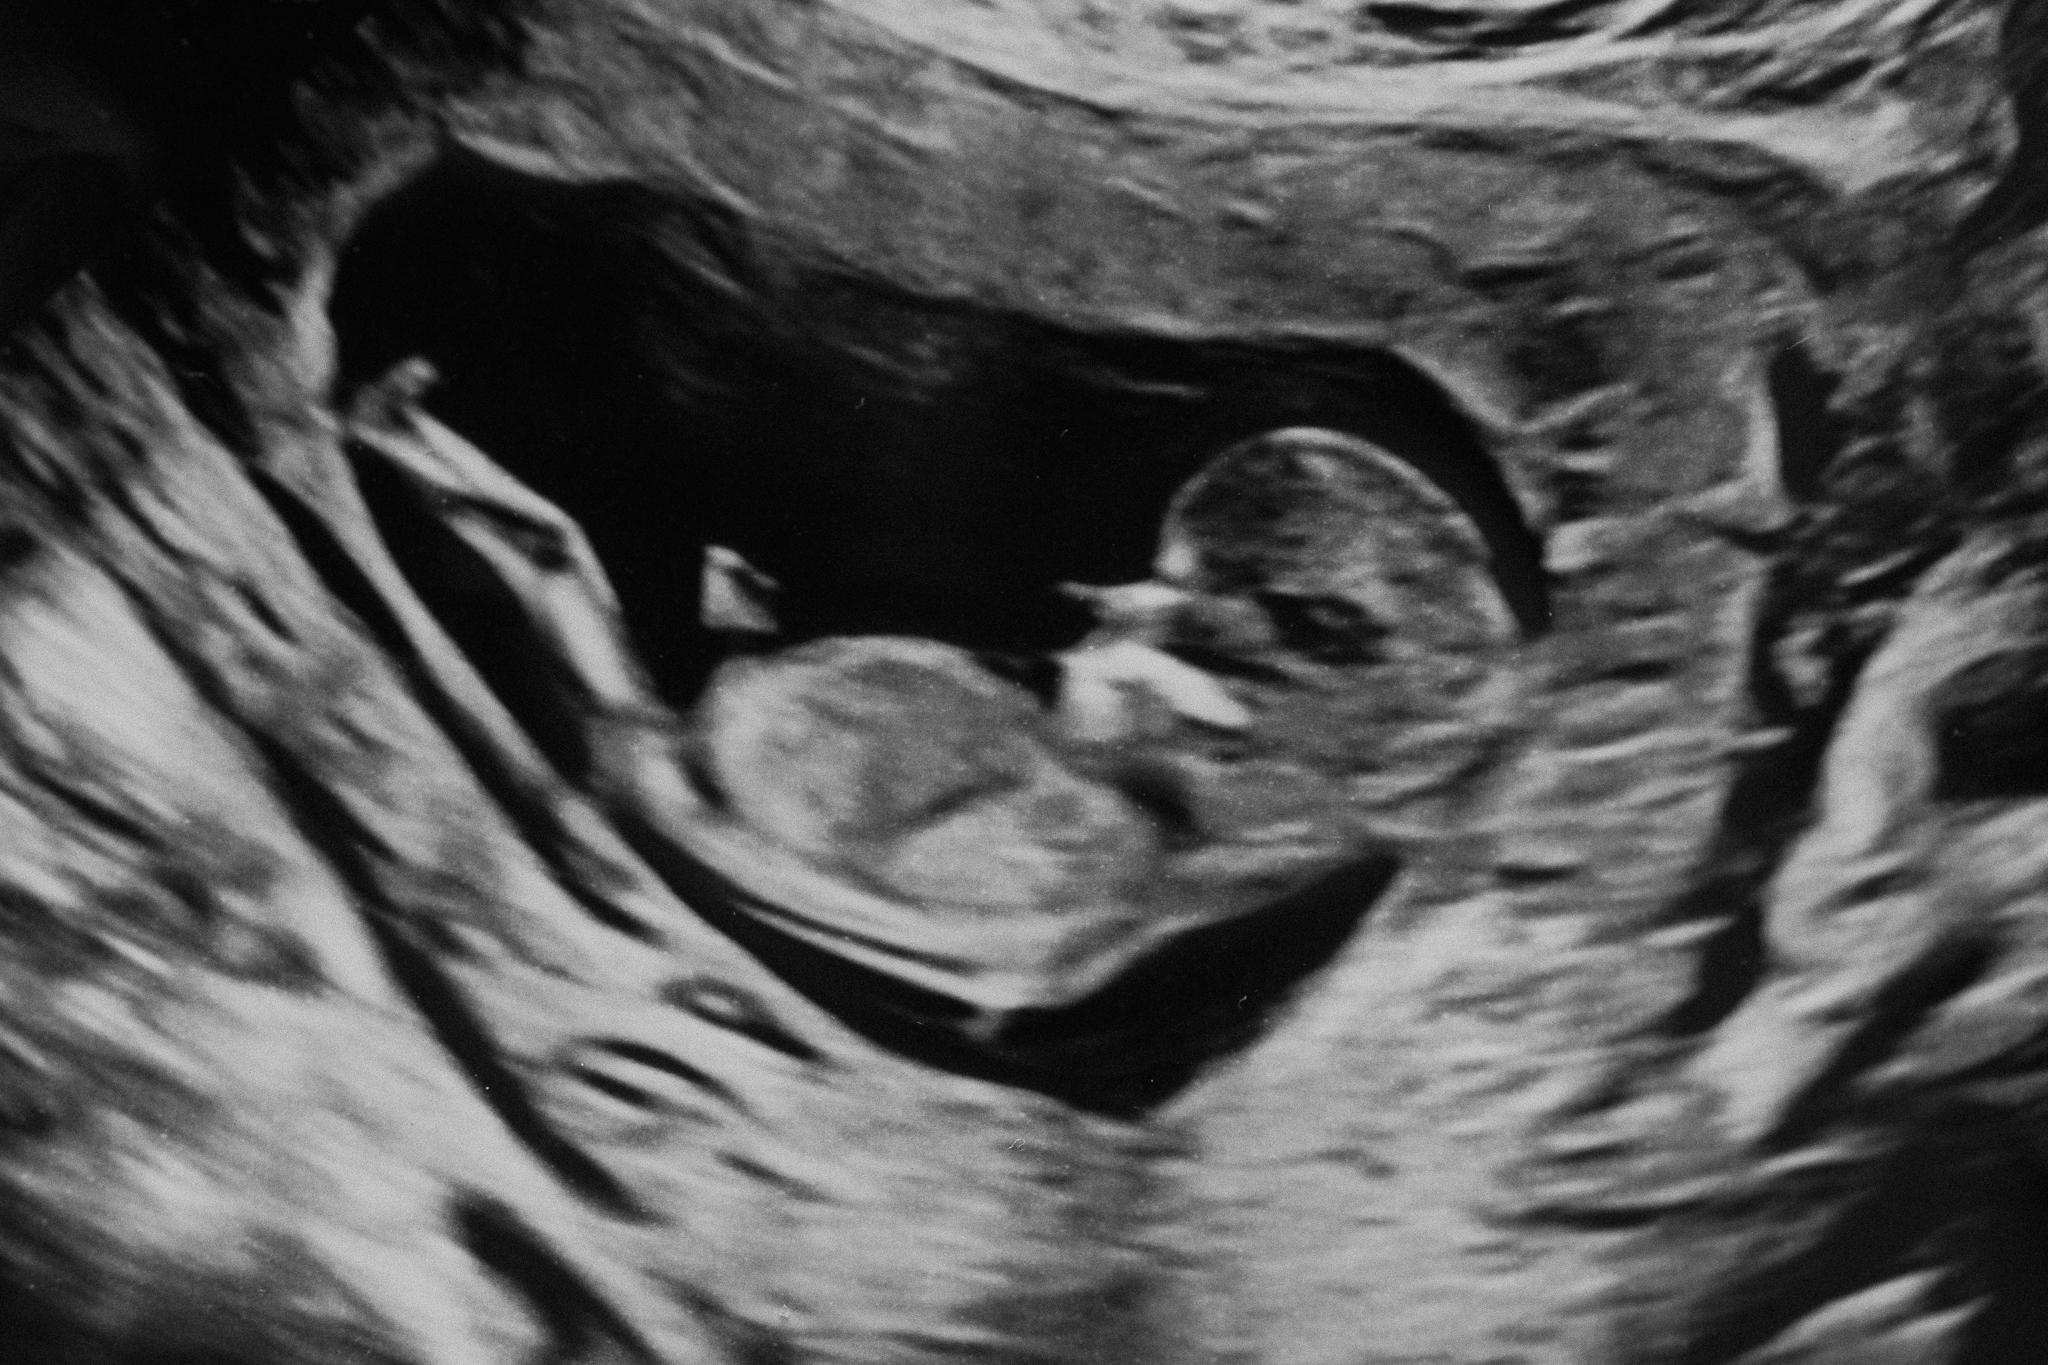

An ultrasound scan of Ophelia's son. Copenhagen, Denmark.